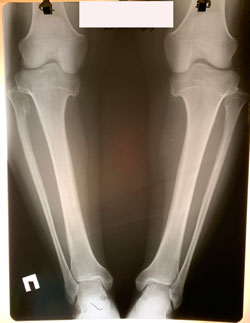

Исходник - 19 лет.

Дата операции - 26.01.2021

Диагноз: Ахондроплазия- низкий рост 149 см

Имеется подвывих головки малоберцовой кости кверху, поэтому: на первом этапе произведено низведение головки малоберцовой кости за счёт удлинения большеберцовой кости на 1,5 см.